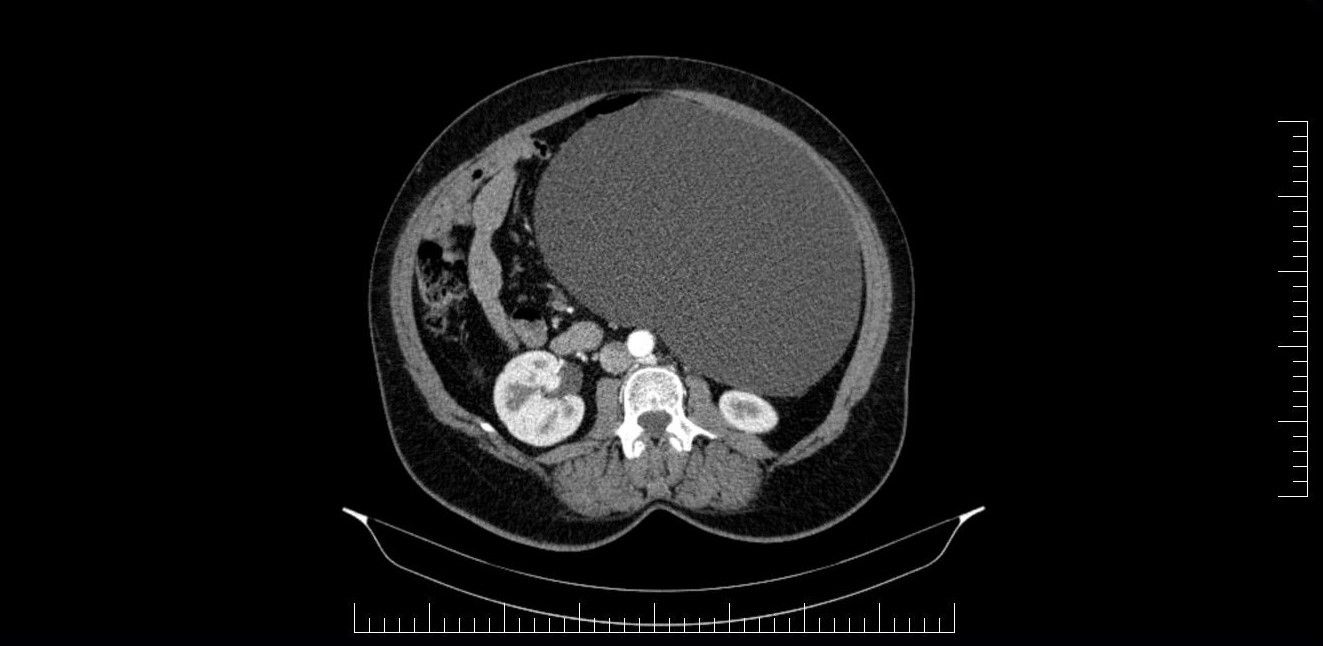

Potrivit reprezentanților Spitalului Militar de Urgență „Dr. Alexandru Augustin” din Sibiu, chistul ovarian de 4,5 kilograme a fost descoperit la o pacientă în urma unui consult ginecologic și a unor investigații în cadrul Laboratorului radiologie și imagistică medicală al Spitalului Militar de Urgență „Dr. Alexandru Augustin” din Sibiu.

„Un chist ovarian voluminos, de 4,5 kg, descoperit la o pacientă, în urma unui consult ginecologic și a unor investigații în cadrul Laboratorului radiologie și imagistică medicală al Spitalului Militar de Urgență „Dr. Alexandru Augustin” din Sibiu (Spital Militar Sibiu – n.red.), a fost operat cu succes de colegul nostru, Remus Maxim, medic primar obstetrică-ginecologie. Existând suspiciunea de neoplasm, medicul din cadrul Compartimentului Ginecologie din Secția Chirurgie Generală a luat decizia de a extrage formațiunea chistică în întregime, operația fiind un succes”.

Postarea a fost însoțită și de imagini pentru a arăta cum se poate schimba conformația corpului, dar și cum arată un chist în organism.